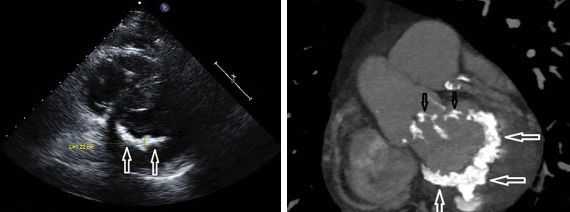

ЭхоКГ может обнаружить тромб с помощью:

- Визуализации подвижного образования на клапане - ее бывает сложно отличить от вегетаций или кальцинированных узелков

- Уменьшение или отсутствие движения подвижной части клапана (например, шара, диска, створок)

- Сопутствующее расширение камер сердца.

- Как и в случае с вегетациями, в M-режиме может отображаться несколько темных эхо-линий и / или уменьшенное открытие или закрытие клапана. Допплерография и ЦДК могут указывать на препятствие для открытия клапана (повышенная скорость потока) или препятствие для закрытия (новая чресклапанная регургитация или увеличение степени тяжести существующей регургитации).

Протезы клапанов на эхокардиографии

Предполагается, что эмболическое событие у пациента после протезирования клапана связано с протезом, пока не будет доказано обратное. Источником эмбола может быть тромбоз клапана, клапанные вегетации или тромб левого предсердия (при митральном протезе). В одной серии пациентов с протезами клапанов, перенесших чреспищеводную эхокардиографию для исследования потенциального источника эмбола, тромб был обнаружен на клапане примерно в 25% случаев. Для механических протезов общая частота тромбоэмболии составляет 0,7-1% на пациента в год для тех, кто лечится антикоагулянтами - гораздо более низкий уровень (4% на пациента в год), чем у тех, кто не использует антикоагулянты. Относительный риск эмболии выше при протезах митрального клапана, чем при протезах аорты, что, скорее всего, связано с более низкой скоростью потока через митральный клапан. Чреспищеводная эхокардиография более предпочтительное исследование для оценки протезов механических клапанов. Из-за акустического затенения поверхность со стороны ЛП не может быть хорошо видна с помощью трансторакального доступа, а протезы аорты обычно лучше видны из чреспищеводного доступа. Вегетации или тромбы на этих клапанах могут выглядеть одинаково, хотя вегетации обычно связаны с конституциональными симптомами и возможной периклапанной регургитацией или частичным раскрытием клапана. Тромб обычно возникает при неадекватной антикоагуляции. Обычно тромб является подвижным на створках клапана и клапанном кольце, связан с эффектом спонтанного эхоконтрастирования и может вызывать обструкцию клапана с повышенным допплеровским градиентом.